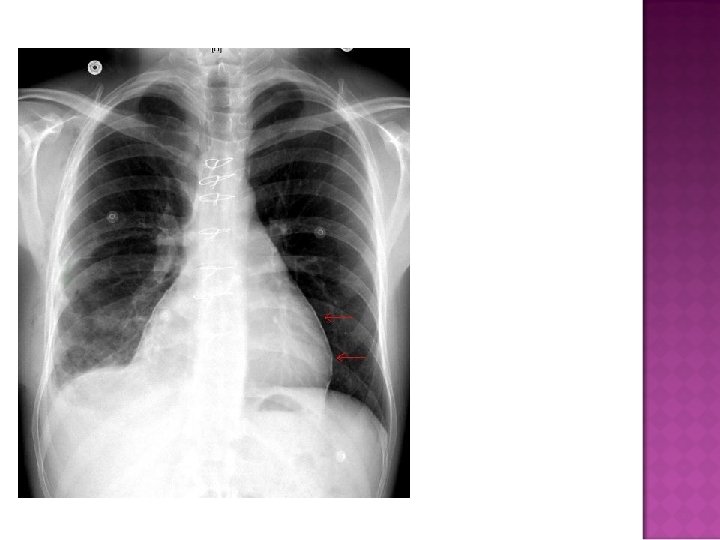

Cardiomegaly due to a massive pericardial effusion. At least 200 m. L of pericardial fluid must accumulate before the cardiac silhouette enlarges.

� Sudden inc in size of cardiac silhouette w/o specific chamber enlargement � Effacement of the normal cardiac borders � Development of a “flask” or “H 2 O-bottle” shaped heart

Normal in patients with acute pericarditis unless pericardial effusion is present Enlarged cardiac silhouette Requires 200 cc of fluid